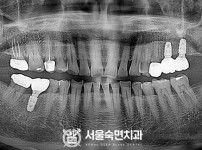

상악동거상술, 뼈이식 / 숙면임플란트 14개 - 네오임플란트 (이*현님)

해당 게시물은 의료법 제56조에 의거하여 로그인 후 열람이 가능합니다.

구분 임플란트